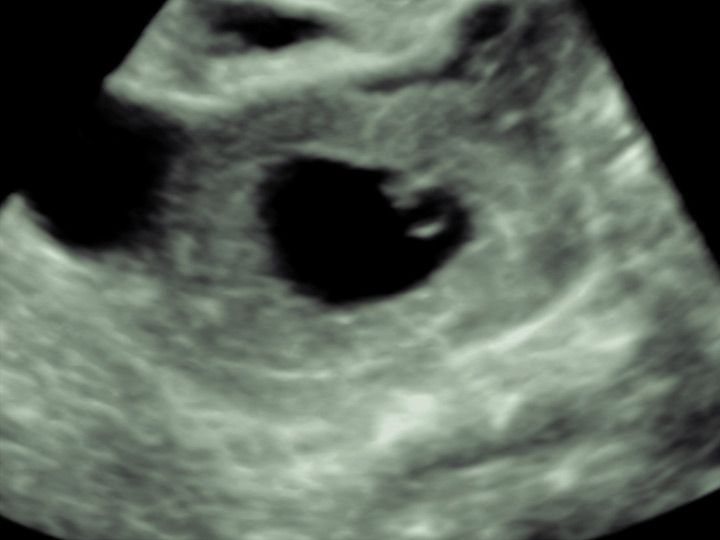

Ovarialkarzinom

In erfahrener Hand kann hier der Verdacht entweder bereits ausgeräumt werden oder eine operative Abklärung in gemeinsamer Planung mit den hiesigen Operateuren eingeleitet werden. Die korrekte Erkennung von bösartigen Befunden des Eierstocks gelingt in erfahrener Hand in über

98% der Fälle.

Veränderungen des Eierstocks sind gerade vor den Wechseljahren häufig funktioneller Natur und durch zyklusbedingte Einflüsse zu erklären. Diese sollten nicht beunruhigen und sind in aller Regel im natürlichen Verlauf abzuwarten. Raumforderungen am Eierstock können aber auch Beschwerden hervorrufen. Zum anderen sollten sie gegen bösartige Veränderungen abgegrenzt werden. Letztere sind selten, jedoch von ungünstiger Prognose, wenn sie ein fortgeschrittenes Stadium erreicht haben.

Die Abgrenzung zwischen einer einfachen funktionellen Veränderung, einer gutartigen Veränderung oder einer potentiell bösartigen Veränderung sollte primär sonographisch erfolgen.